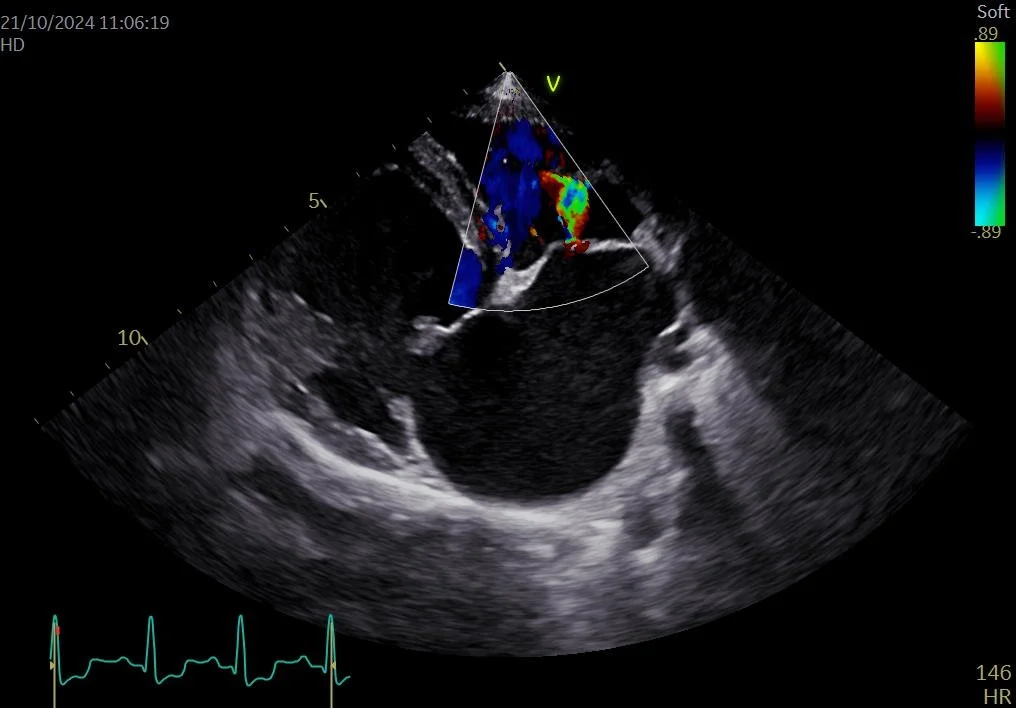

Echo acquired interatrial septal defect in dog with myxomatous mitral valve disease

• Myxomatous mitral valve disease with complications